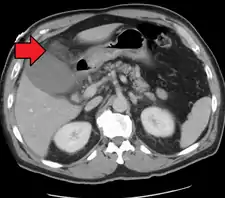

قد يُسبب سرطان المرارة هجماتٍ من الألم المراري وانصباغ الجلد باللون الأصفر (يرقان) وفقدان الوزن، وإذا كانت المرارة كبير قد يُمكن لمسها في البطن، كما أنَّ اختبارات وظائف الكبد قد ترتفع، وخاصةً ناقلة الببتيد غاما غلوتاميل (GGT) والفوسفاتاز القلوي (ALP). يُمكن استخدام التصوير المقطعي المحوسب والتصوير بالموجات فوق الصوتية، واللذان أصبحا من وسائل التصوير الطبي المُفضلة في هذه الحالة.[8] يتم التعامل مع سرطان المرارة باستئصال المرارة، ولكن اعتبارًا من عام 2010 لا يزال مآل المرض ضعيفًا.[8]

عادةً ما يكون التصوير بالموجات فوق الصوتية أولَ فحصٍ تصويريٍ طبيٍ يُنفذُ مع أمراض المرارة مثل الشك بوجود حصواتٍ صفراوية.[8] من طُرق التصوير الأُخرى التصوير بالأشعة السينية للبطن أو التصوير المقطعي المحوسب، حيثُ قد تستخدم لفحص المرارة والأعضاء المحيطة بها.[8] يُمكن أيضًا استعمال خياراتٍ تصويرية أُخرى مثل تصوير البنكرياس والأوعية الصفراوية بالرنين المغناطيسي (MRCP) وتصوير البنكرياس والأقنية الصفراوية بالتنظير الباطني بالطريق الراجع (ERCP) وتصوير الأوعية الصفراوية بطريق الجلد أو أثناء العملية.[8] التصوير الومضاني الصفراوي هو تصويرٌ نووي يُستعمل لتقييم حالةِ المرارة.[45]